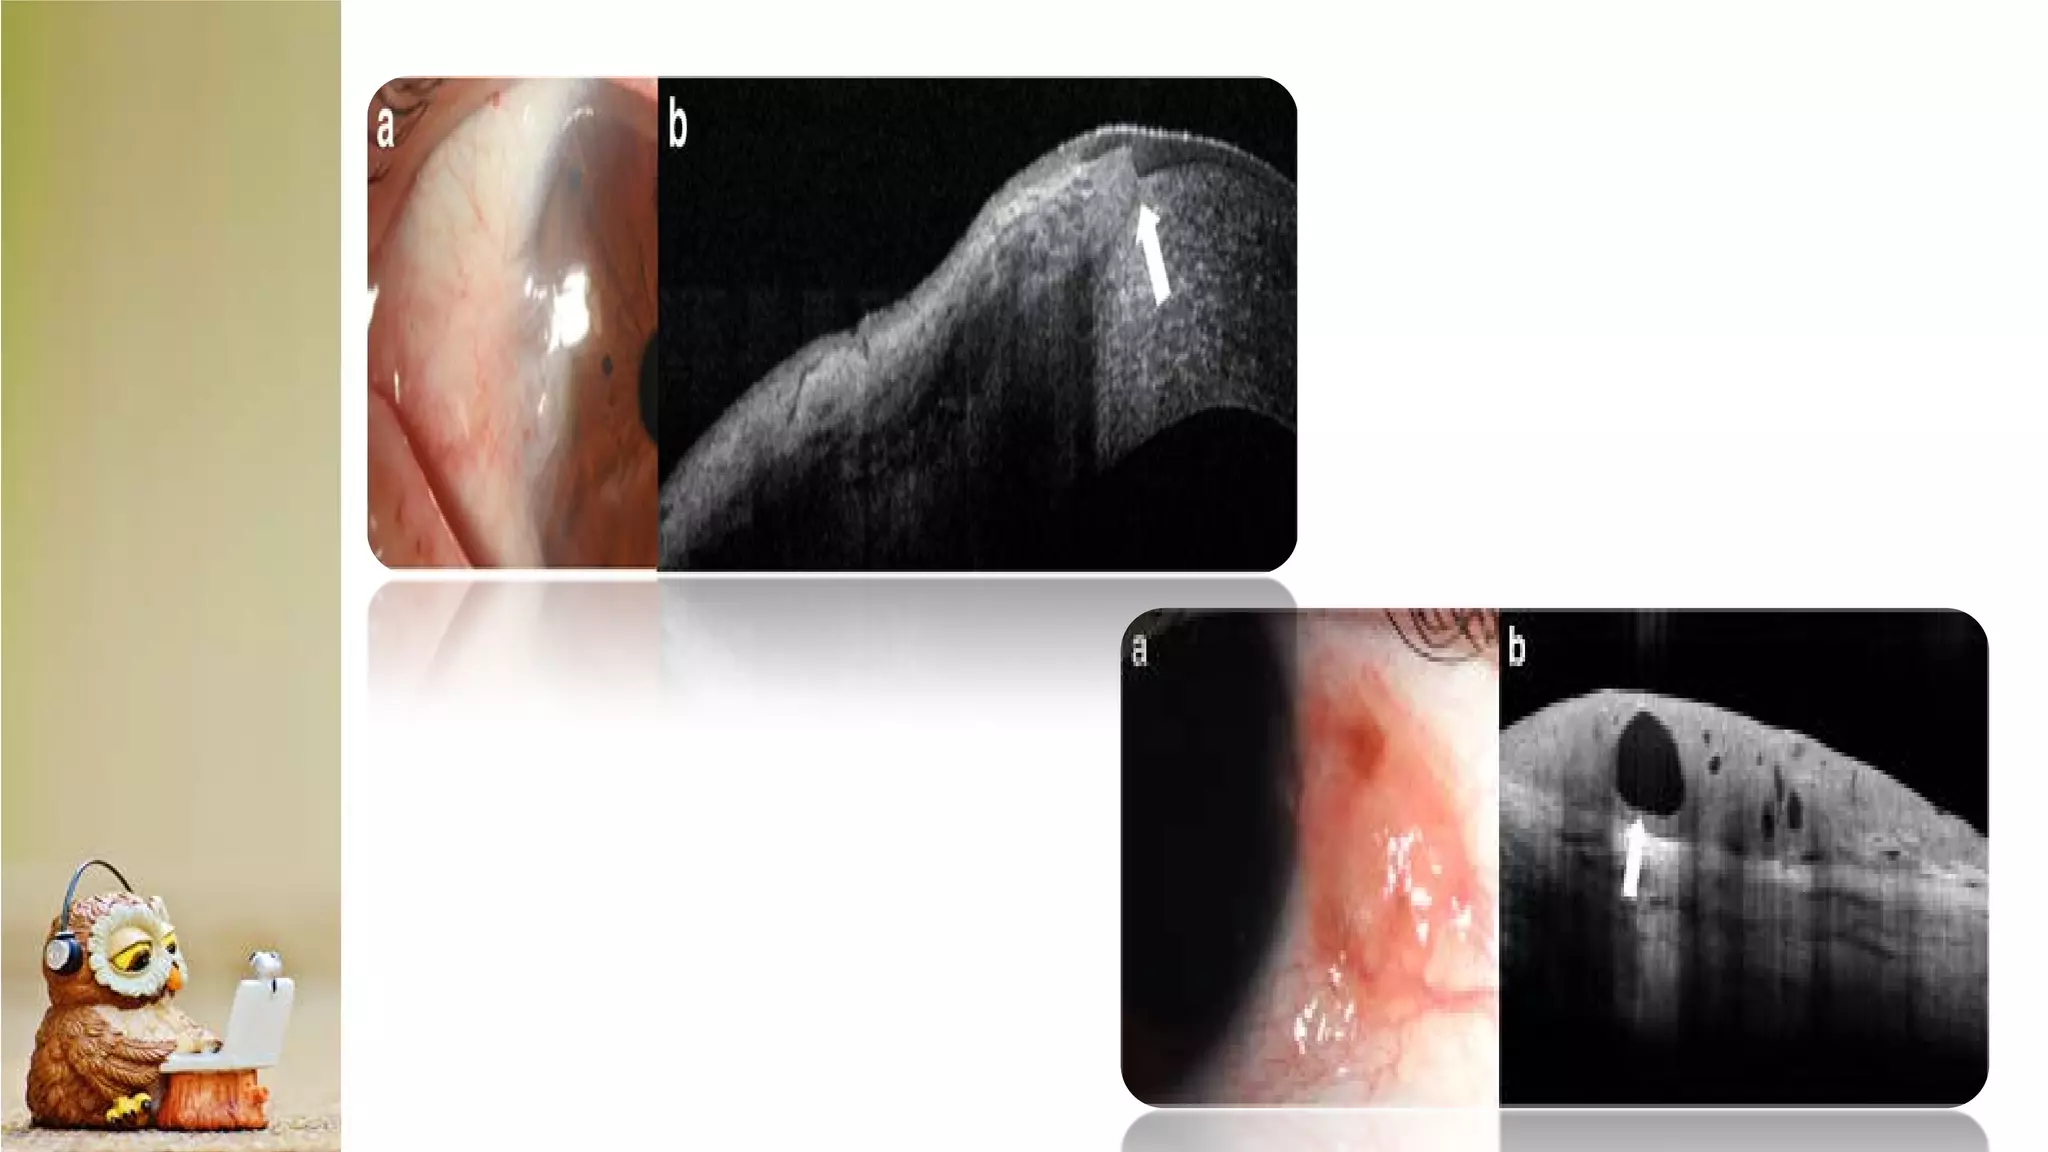

The document discusses Anterior Segment Optical Coherence Tomography (AS-OCT) as a noninvasive diagnostic tool providing high-resolution cross-sectional images of the ocular surface and anterior segment. It details various OCT devices, their manufacturers, measurement types, and scanning speeds, highlighting qualitative and quantitative assessment capabilities. The document also notes limitations such as resolution modes and specific ocular conditions that may affect results.